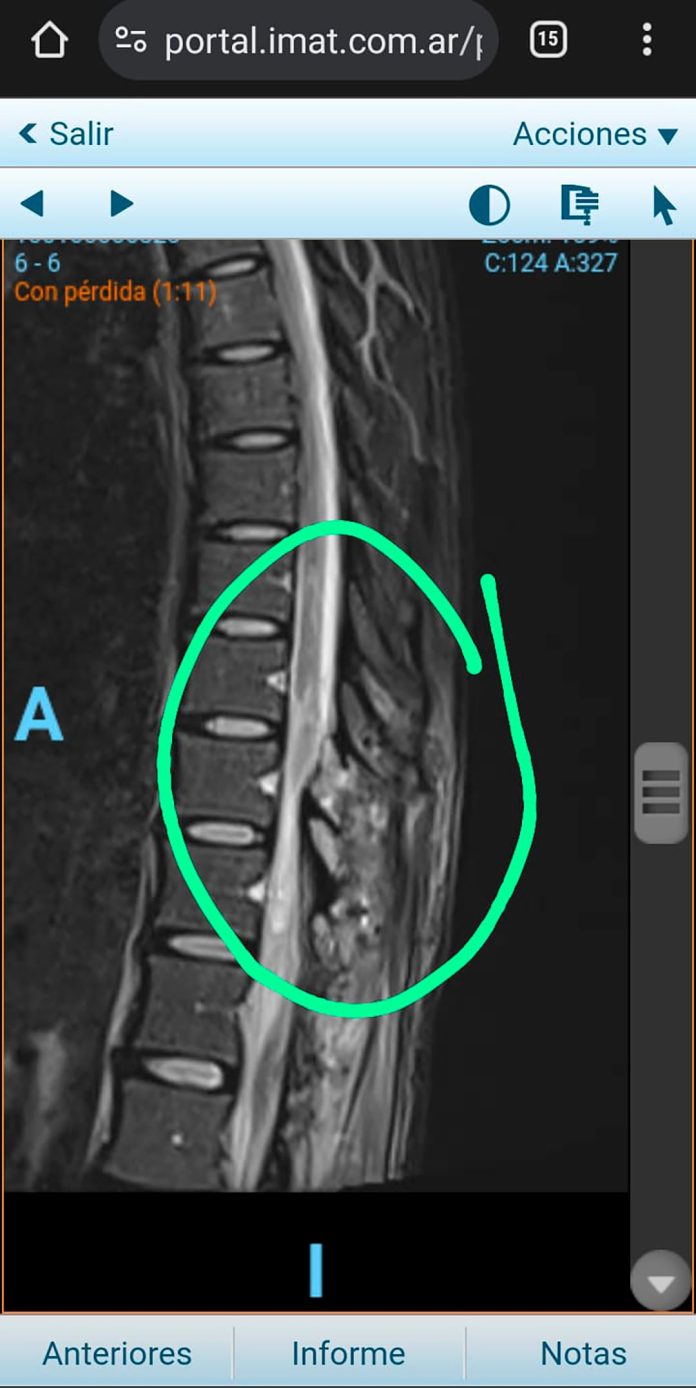

La placa que muestra la lesión que le generaron en la médula

El diagnóstico llegó recién el 2 de marzo: Antonella tenía una “apófisis espinal que le estaba comprimiendo la médula”. Esto significa que, tras la operación, una parte del hueso de la columna quedó haciendo una presión que le ocasionaba diferentes problemas. Por eso tuvieron que intervenirla de urgencia para descomprimir el canal medular.